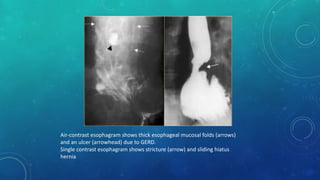

Air-contrast esophagram shows thick esophageal mucosal folds (arrows)

and an ulcer (arrowhead) due to GERD.

Single contrast esophagram shows stricture (arrow) and sliding hiatus

hernia